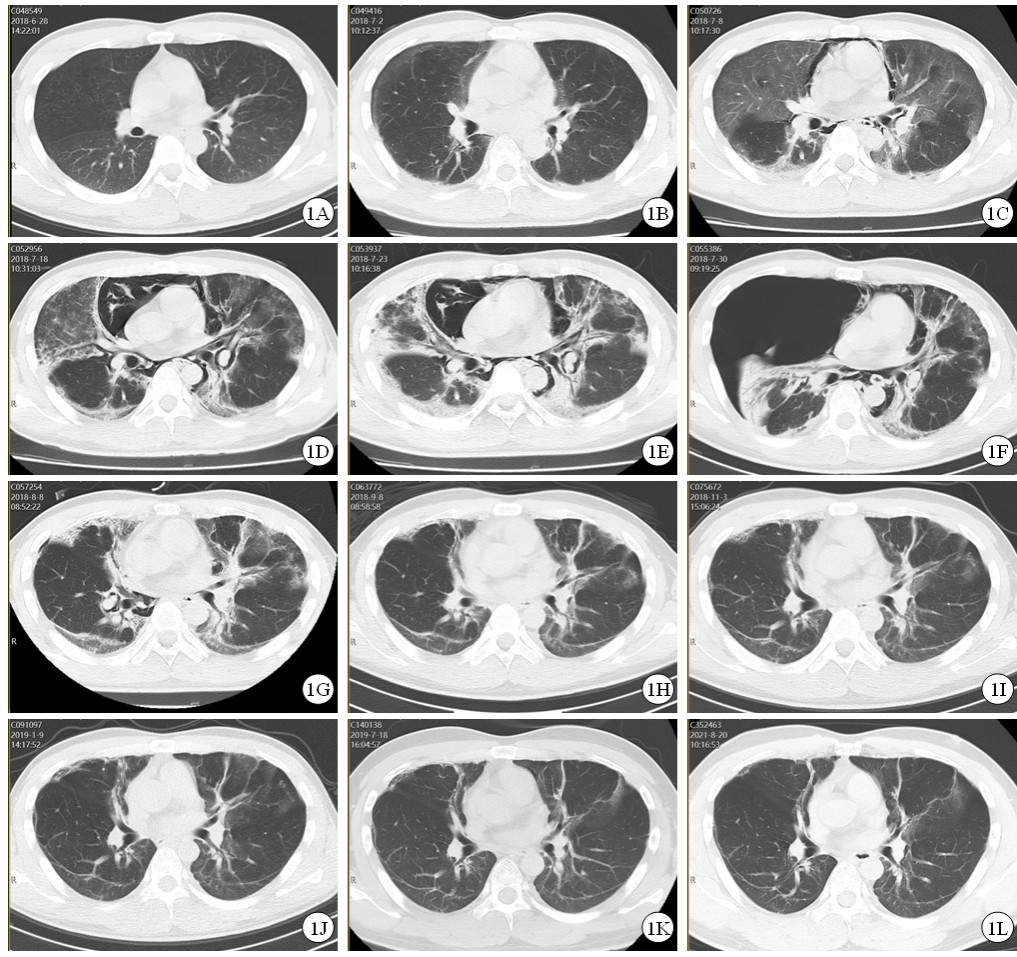

治疗效果:患者治疗过程中给予持续心电监护、血氧饱和度监测、血压监测、记出入量,动态监测肝肾功能变化(表 1)。入院12 h后尿液中PQ含量降至10~30 mg/L,入院18 h后尿液中PQ含量降至0~3 mg/L。入院第2天出现口腔黏膜充血,咽部疼痛,血肌酐升高,PaCO2: 35mmHg,PaO2:115 mmHg,Lac: 3.9 mmol/L;第3天出现顽固性呃逆,间断予以氯丙嗪肌肉注射,PaO2: 103 mmHg,Lac: 4.5 mmol/L,胸部CT:双肺下叶条索灶(图 1A);第5天口咽黏膜糜烂疼痛加重,全身皮肤黏膜黄染,肝功能相关指标明显升高,PaO2: 92 mmHg,Lac: 1.5 mmol/L;第7天未再出现呃逆,PaO2: 90 mmHg,Lac: 1.4 mmol/L,胸部CT:双肺间质性改变,双侧胸腔积液(图 1B);第12天肾功能相关指标恢复正常,肝功能相关指标开始好转,PaO2: 63 mmHg;第13天胸部CT:纵隔、颈部及胸壁气肿,双肺间质纤维化范围较前增大,双侧胸腔少量积液(图 1C);第23天口咽部疼痛明显减轻,PaO2: 74 mmHg,胸部CT:纵隔气肿及皮下气肿较前加重,双肺间质弥漫磨玻璃样影及条索状高密度灶较前密度增高,肺组织较前膨胀不全,双侧胸腔仍见少量积液(图 1D);第28天胸部CT示纵隔气肿及皮下气肿、双肺间质性肺炎并纤维化、肺组织膨胀不全较前较前持续加重(图 1E);第31天肝功能相关指标恢复正常;第35天患者突发胸闷憋气,胸部CT示右侧大量气胸、纵隔偏移(图 1F),急症行胸腔闭式引流术后,症状缓解;第42天PaO2: 87 mmHg,胸部CT示右侧胸膜腔及纵隔内气体较前明显减少,双肺间质弥漫磨玻璃样影及条索状、斑片状高密度灶较前减轻(图 1G);第44天出院。服毒半年后,患者自述无胸闷、憋气、胸痛等不适,步行上五楼无明显气促症状,PaO2: 76 mmHg,胸部CT:双肺间质弥漫磨玻璃样影及条索状、斑片状高密度灶,范围较前缩小,边缘较前清晰(图 1J)。服毒1年后,患者可从事正常体力劳动,PaO2: 91 mmHg,胸部CT: 双肺野内示多发纤维条索灶,胸膜下线形成,肺纤维化复查好转CT表现(图 1K)。服毒3年后,患者已从事正常体力劳动,PaCO2: 39 mmHg,PaO2: 82 mmHg,胸部CT:双肺野内示多发纤维条索灶,胸膜下线形成,较前未见明显变化(图 1L)。